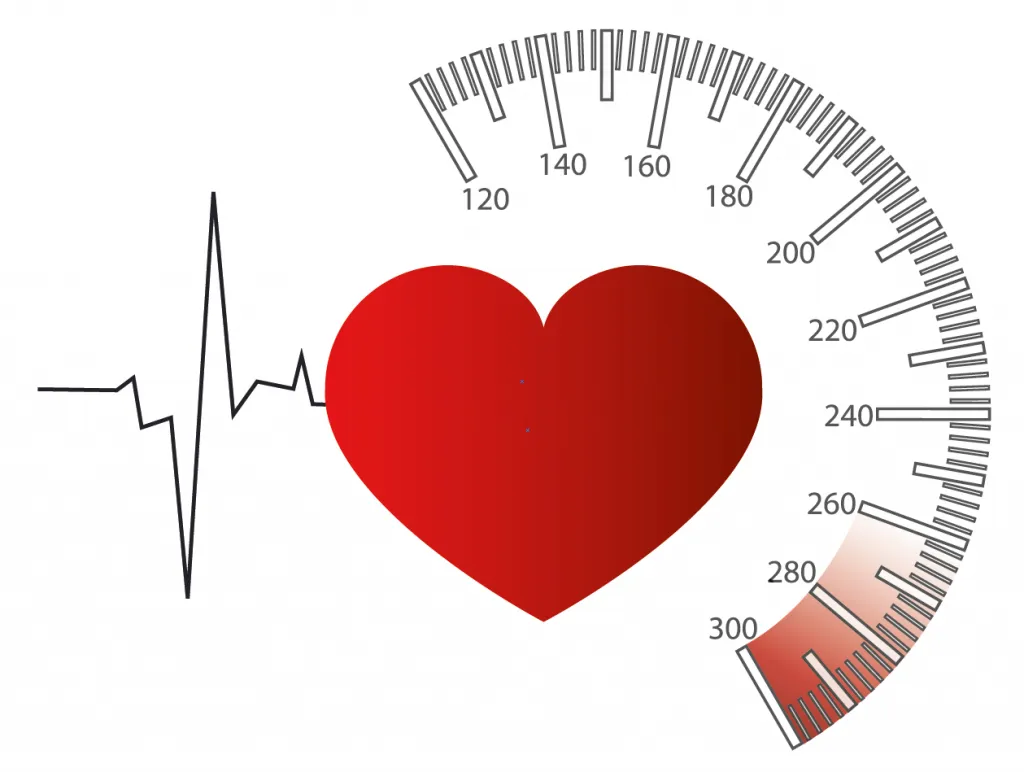

Tăng huyết áp nặng gồm 2 thể: cấp cứu (HA ≥ 180/120 mmHg kèm tổn thương cơ quan đích) và khẩn trương (HA tăng cao nhưng không tổn thương cơ quan). Cấp cứu cần hạ áp nhanh bằng thuốc tiêm, theo dõi...

Tăng huyết áp nặng gồm 2 thể: cấp cứu (HA ≥ 180/120 mmHg kèm tổn thương cơ quan đích) và khẩn trương (HA tăng cao nhưng không tổn thương cơ quan). Cấp cứu cần hạ áp nhanh bằng thuốc tiêm, theo dõi...